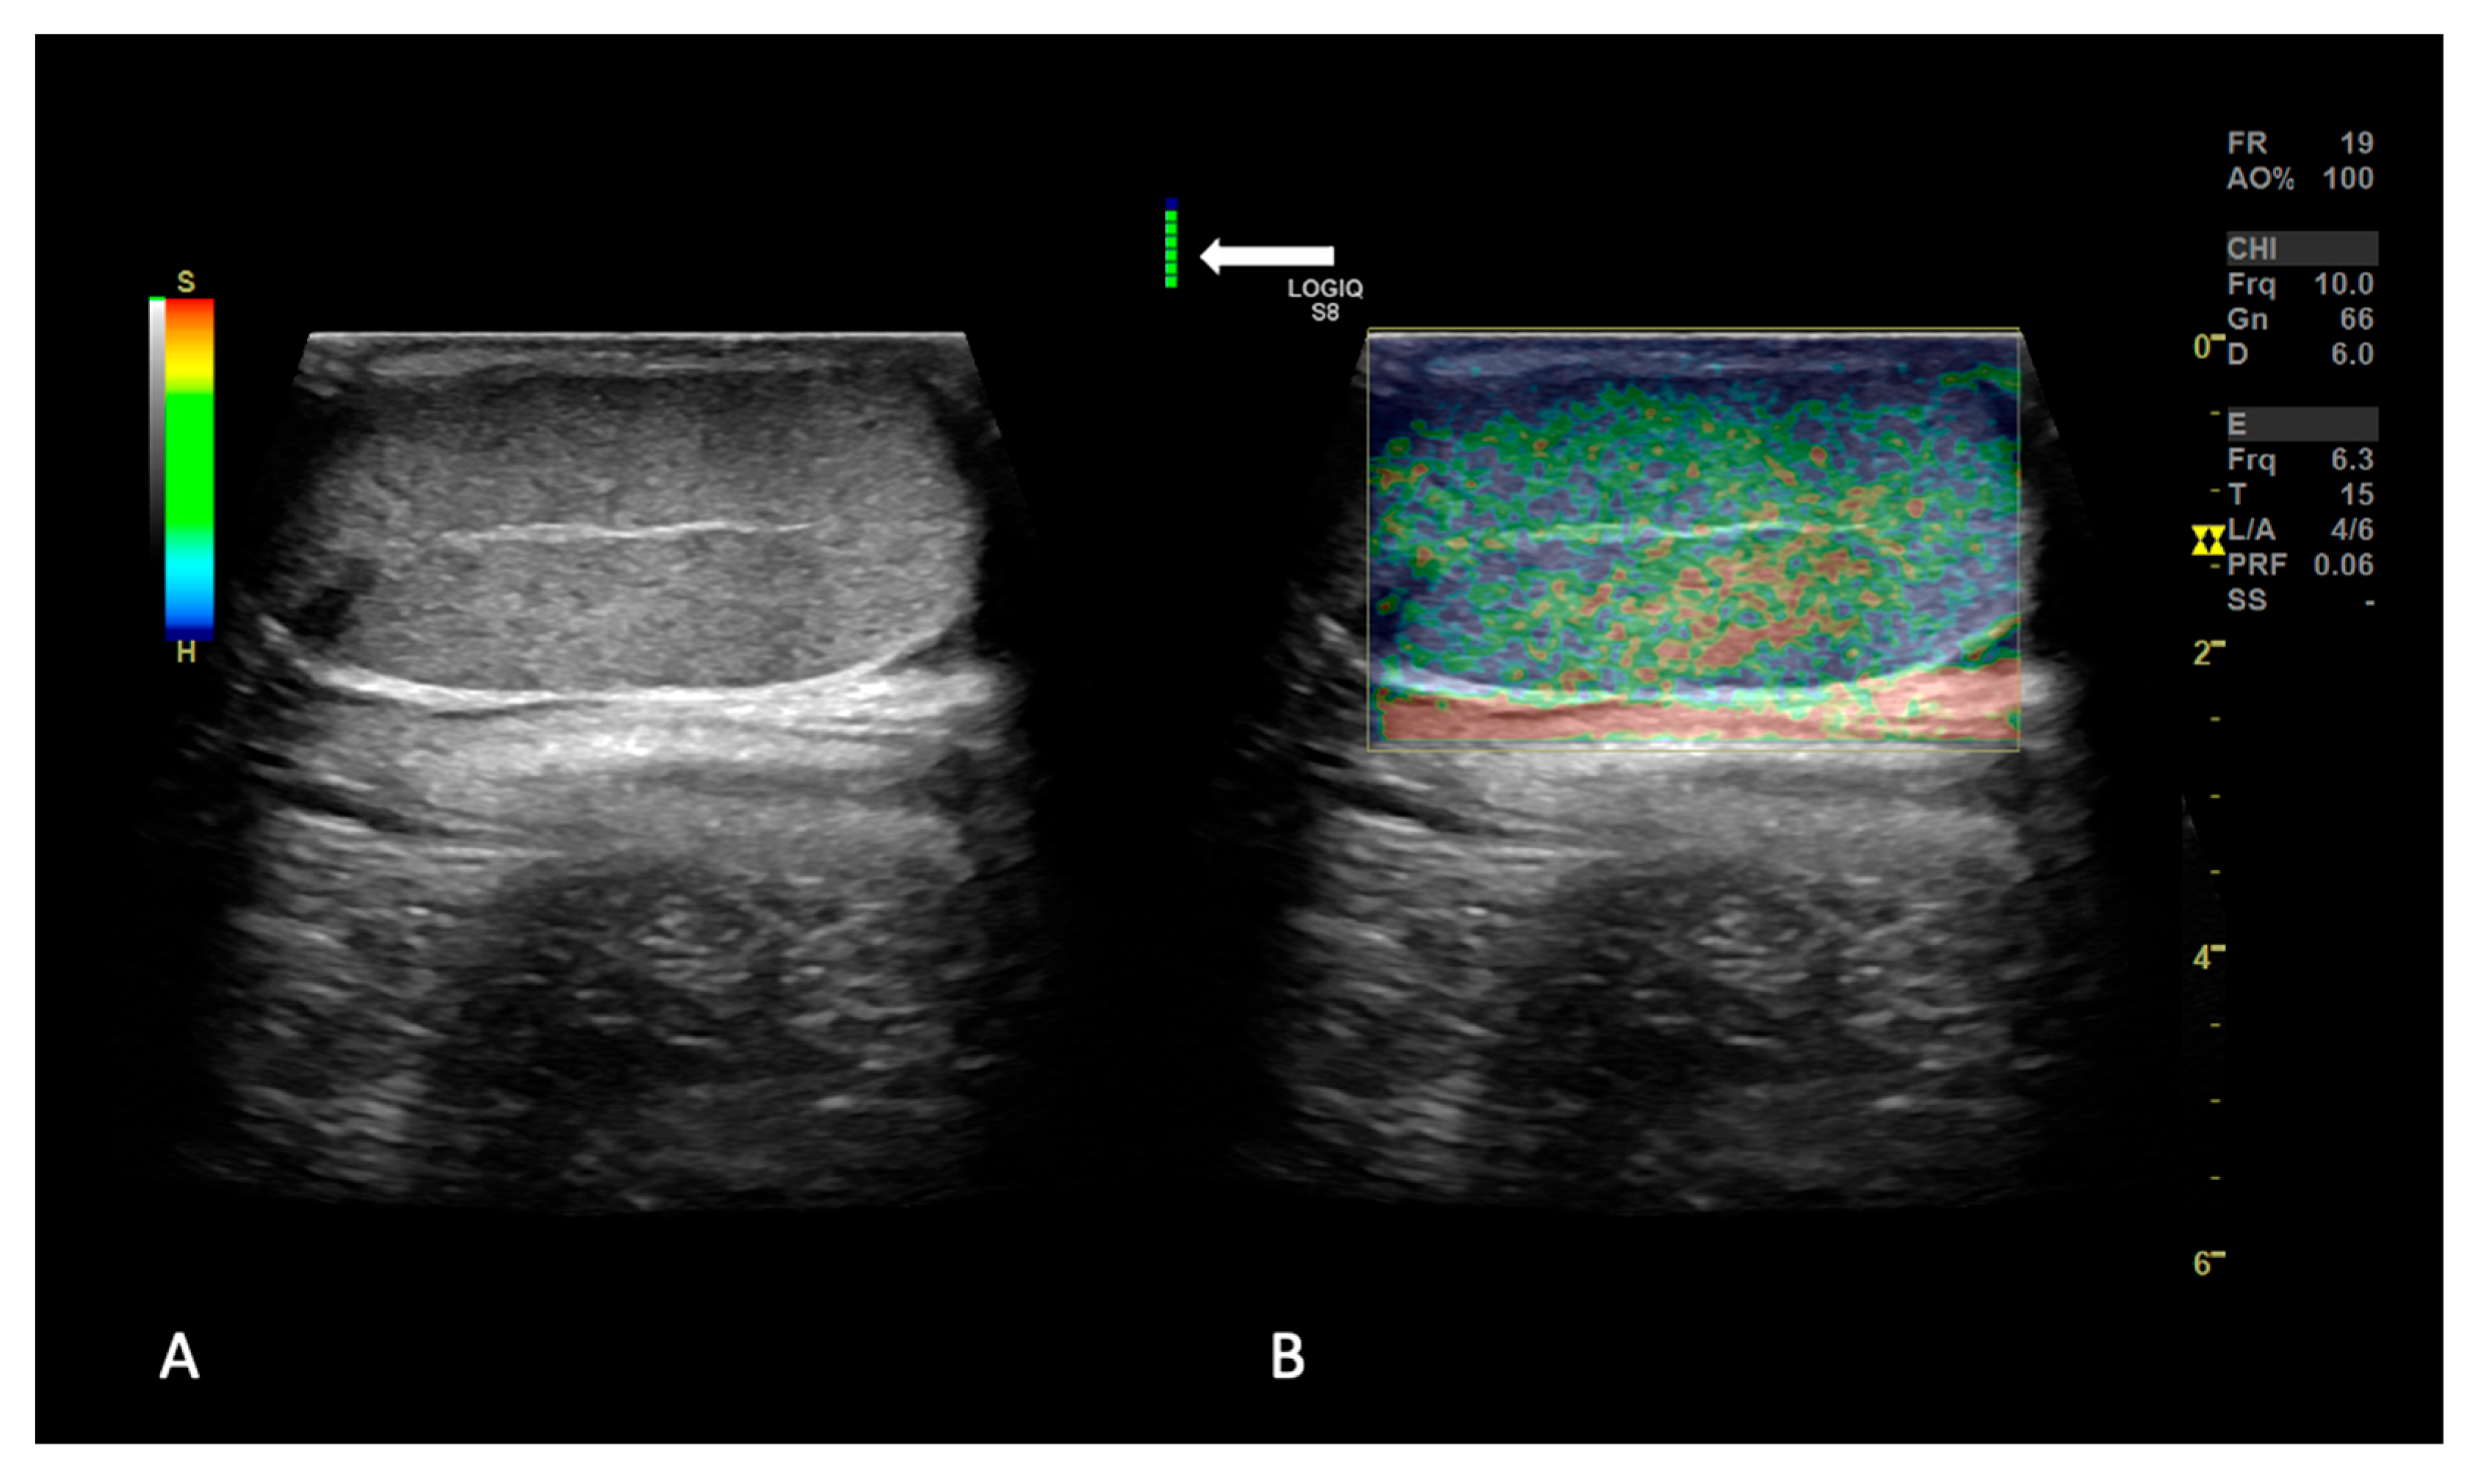

2.1.2. SE and 2D SWE Examination

3.2. Strain Elastography Evaluation